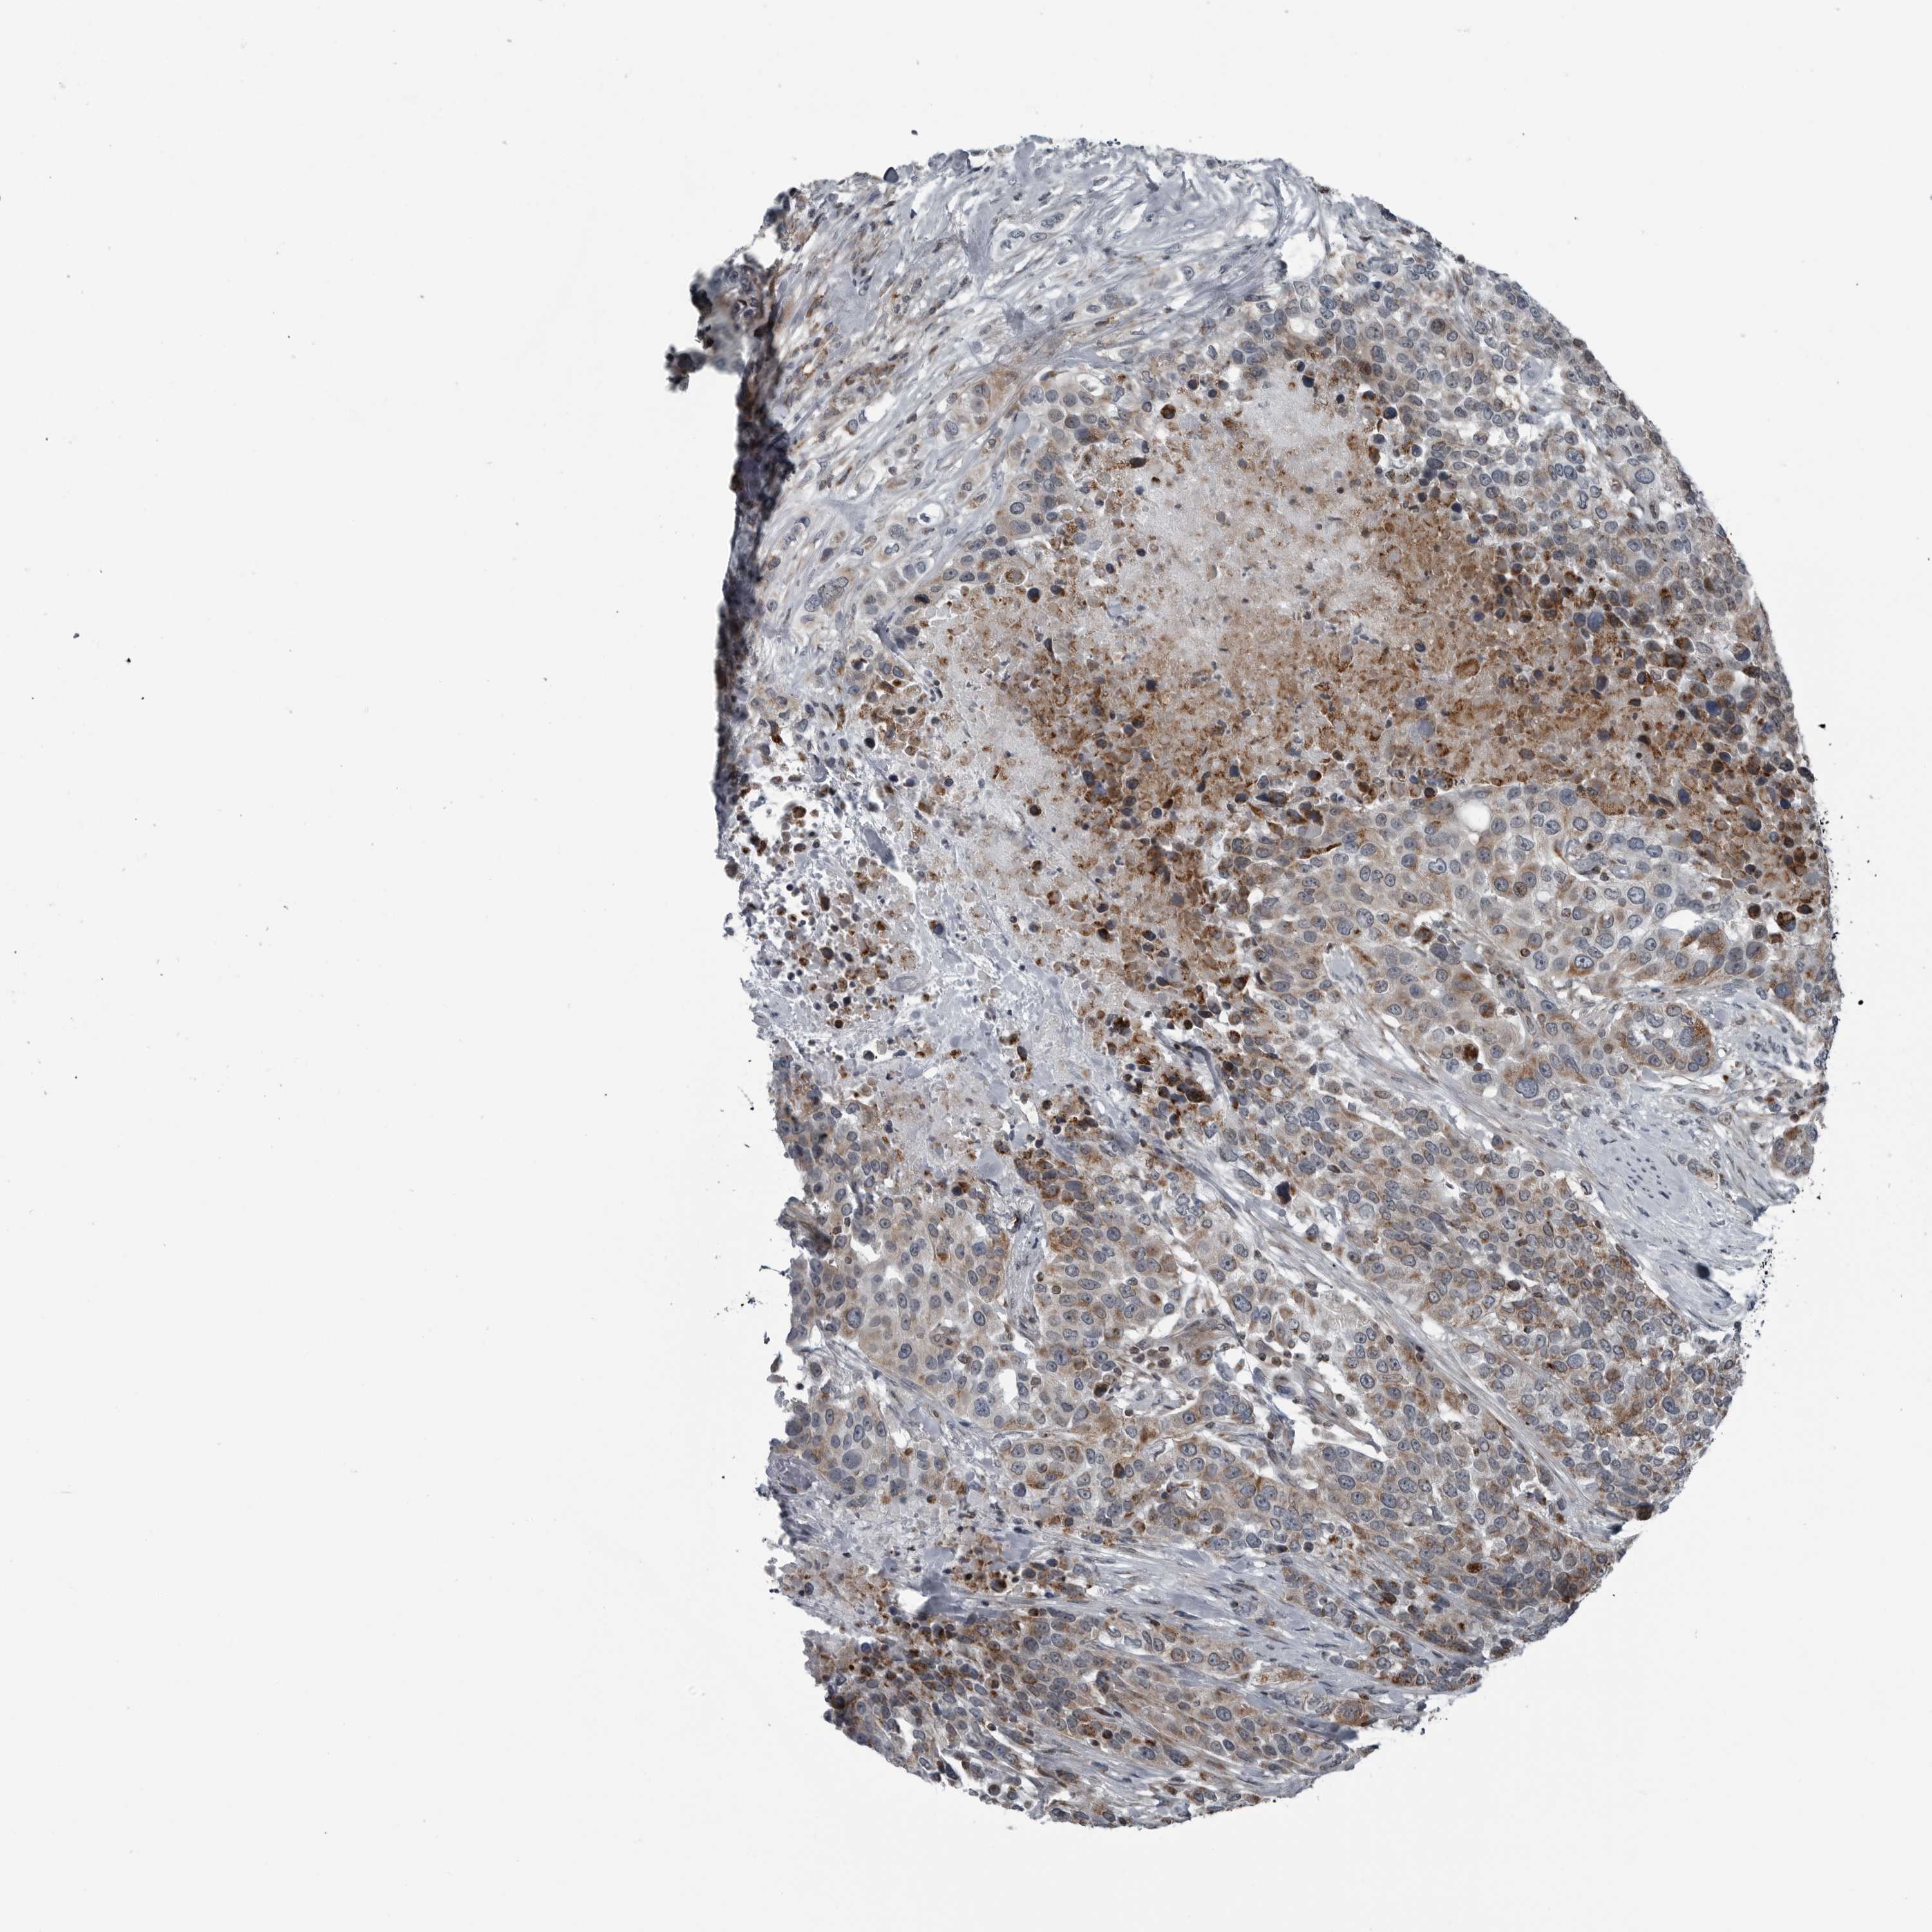

UROTHELIAL CANCER - Protein expressioni

A mouse-over function shows sample information and annotation data. Click on an image to view it in a full screen mode. Samples can be filtered based on level of antibody staining by selecting one or several of the following categories: high, medium, low and not detected. The assay and annotation is described here.

Note that samples used for immunohistochemistry by the Human Protein Atlas do not correspond to samples in the TCGA dataset.

Antibody stainingi

Antibody staining in the annotated cell types in the current human tissue is reported as not detected, low, medium, or high, based on conventional immunohistochemistry profiling in selected tissues. This score is based on the combination of the staining intensity and fraction of stained cells.

Each image is clickable and will lead to virtual microscopy that enables deeper exploration of all samples and also displays staining intensity scores, fraction scores and subcellular localization as well as patient and tissue information for each sample.

Antibody HPA027405

Antibody HPA027459

Antibody HPA027463

Staining

High

Medium

Low

Not detected

Intensity

Strong

Moderate

Weak

Negative

Quantity

>75%

75%-25%

<25%

None

Location

Nuclear

Cytoplasmic/membranous

Cytoplasmic/membranous,nuclear

Urothelial carcinoma, Low grade

Urothelial carcinoma, High grade